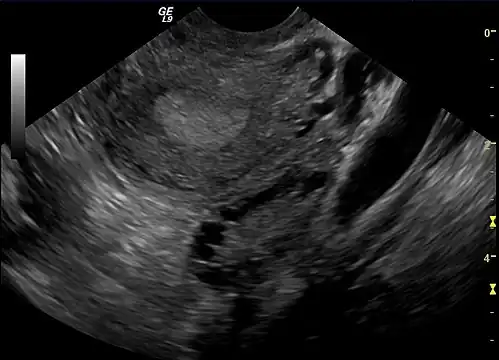

Gynecologic ultrasonography first looks for small ovarian follicles.[75] To count as polycystic ovaries, at least 20 follicles need to be present, smaller than 9 mm. This used to be 12 in older diagnostic criteria.[16] A less clear marker of PCOS is enlarged ovaries.[75] Ovary need to be at least 10 cm3 to count.[16] For sexually active individuals or those that agree, a transvaginal ultrasound approach is preferred. Alternatively, AMH levels can be tested in the blood.[75] Laparoscopic examination may reveal a thickened, smooth, pearl-white outer surface of the ovary. This would usually be an incidental finding if laparoscopy were performed for some other reason, as it would not be routine to examine the ovaries in this way to confirm a diagnosis of PCOS.[78]

-

Transvaginal ultrasound scan of polycystic ovary -

Polycystic ovary as seen on sonography